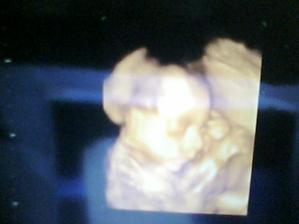

Takže test na cukrovku máme v normě, tak jsme mooc rádi, že můžeme mlsat a že nejsou žádné zbytečné komplikace. Na Tadeáška se půjdeme podívat 4D ultrazvukem, už se na něj mooc těším, jdeme tam 27.10.2009. Tak pak přihodím nějaké foto 🙂)

Tak, 4D ultrazvuk vřele doporučuji, byl to nádherný zážitek, viděli jsme Tadeáška, jak vypadá. Je moc nádherný, mamince ukápla i slzička. Máme i DVD, tak na něj pořád koukám. Zrovna spinkal, tak byl v klidu, taťka ho nechtěl vzbudit.